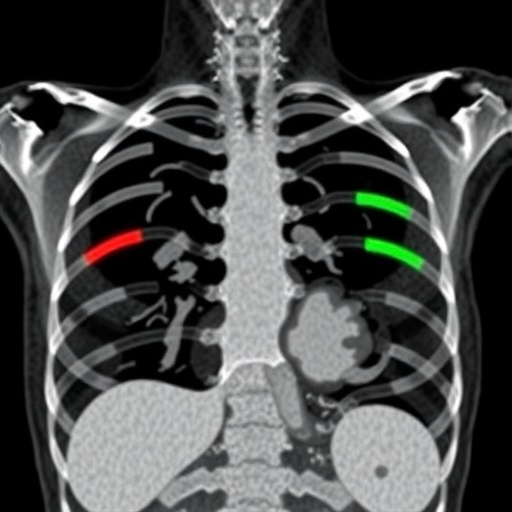

Rib fractures constitute a critical indicator in the forensic evaluation of trauma-related deaths, often shedding light on the circumstances surrounding fatal injuries. Postmortem CT imaging has increasingly become a valuable modality in forensic examinations due to its ability to non-invasively visualize the internal structure of the thoracic cage in exquisite detail. However, the sheer volume and complexity of CT data present substantial analytical burdens. This new study recognizes the urgent need for computational tools capable of navigating these challenges. By applying state-of-the-art deep learning algorithms, specifically designed convolutional neural networks (CNNs), the researchers have developed a robust framework that processes volumetric CT data to automatically identify rib fractures with high accuracy.

The design of the deep learning model involved training on a large dataset of postmortem CT scans, meticulously labeled by forensic radiologists to ensure ground-truth reference. This supervised learning paradigm enabled the network to discern intricate fracture patterns and subtle degenerative changes that often complicate manual evaluation. The model leverages advanced convolutional layers configured to capture three-dimensional contextual information, enhancing the system’s ability to differentiate between pathological rib deformities and genuine fractures caused by trauma. Early validation results demonstrate remarkable sensitivity and specificity metrics, evidencing the potential for clinical and forensic adoption.

Technically, the implementation underscores several innovations in handling postmortem CT image data. The team tackled the challenge of heterogeneous image quality and variable artifact presence, which are typical in postmortem scans due to decomposition and handling conditions. Through sophisticated image pre-processing pipelines and augmentation strategies, the model’s input data was homogenized, allowing it to generalize across diverse cases. Importantly, the use of three-dimensional CNN architectures marks a significant leap from conventional two-dimensional slice-based analyses, facilitating a holistic interpretation of rib cage morphology and fracture connectivity.